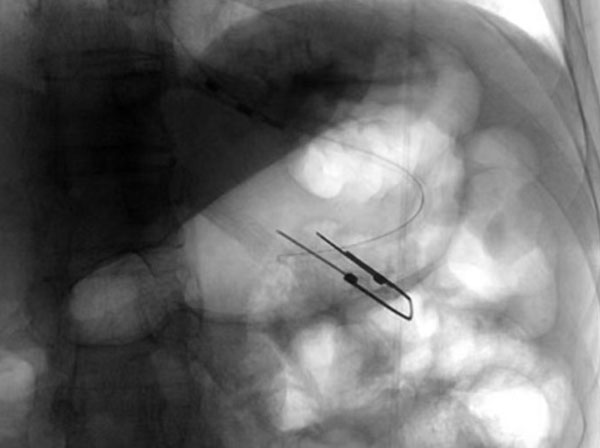

沒有營養支持,患者無法進一步治療,建立腸內營養通路迫在眉睫。放射科介入團隊創新性提出全麻護航的手術方案,楊光主任與麻醉科溝通后,為患者制定了個體化鎮靜鎮痛策略,同時采用聯合DSA透視下的精準引導,快速將導絲及導管經口鼻迅速置入胃腔內,短時間內精準定位穿刺點,操作時間僅用15分鐘。患者術中無不良反應,術后5分鐘即恢復意識,造瘺管引流通暢,實現了全程無痛介入。